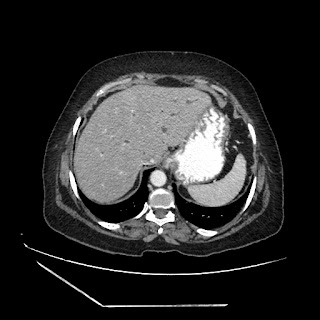

A 70 years old woman with Obstractive jaundice & palpable GB